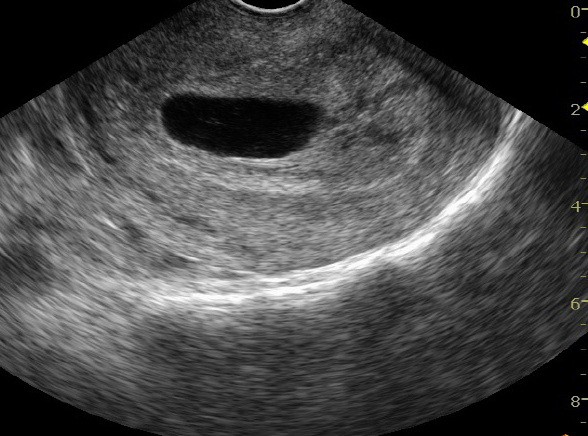

Кухо яйце

Публикувано на: 09.01.2007 Какво представлява “кухото яйце”? Кухото яйце (също извeстно като “бременност без ембрион”) се получ...